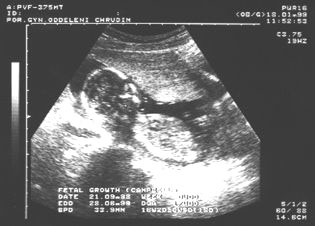

10. týden: dvojvaječná dvojčata

10.týden